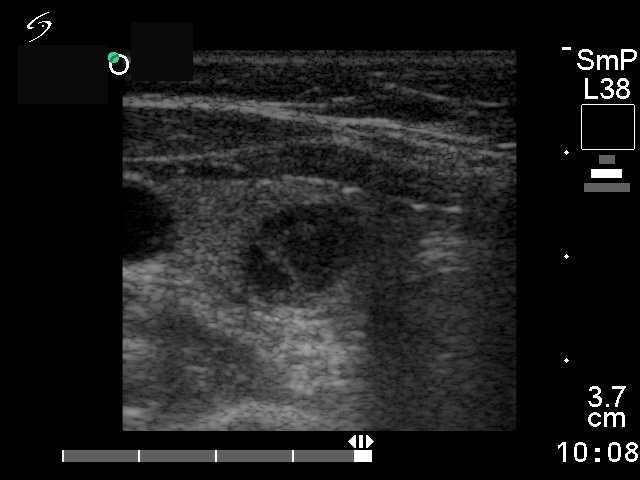

Follicular adenoma - Case 29